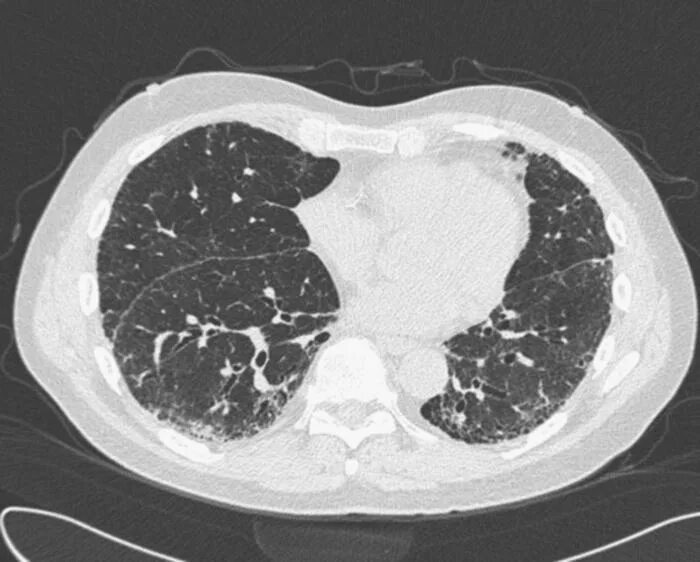

Гипостатические изменения кт